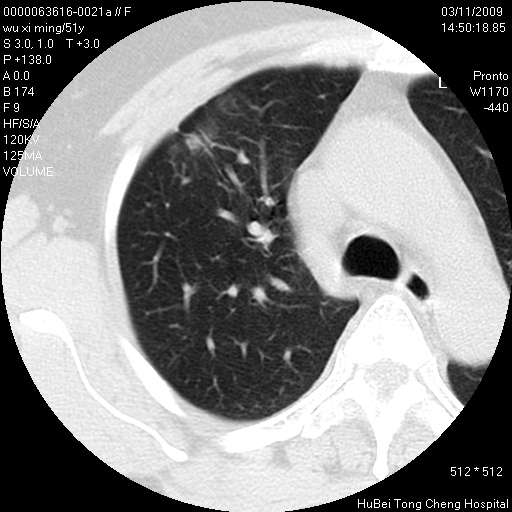

患者 女,51岁。因“胆囊炎,胆囊结石”,行常规术前胸部x线检查发现:右上肺结节病灶,建议行进一步检查。患者无咳嗽、咳痰及咯血等呼吸道症状,近期出现背部疼痛不适。

胸部ct轴位平扫(层厚10mm,螺距1.5,重建间隔10mm;部分层面:层厚3mm,螺距1.0,重建间隔3mm),图像如下:

右肺周围型肺癌伴肺内转移信胸椎转移

右肺周围型肺癌伴肺内转移及胸椎转移。已无手术机会。